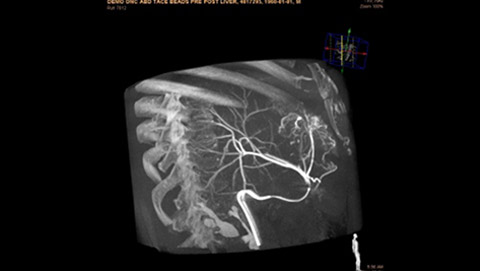

Dynamic 3D Roadmap provides a sustainable 3D roadmap to support interventional procedures. Dynamic 3D Roadmap matches the real-time 2D fluoroscopy images with the 3D-RA reconstruction of the vessel tree. It provides a 3D real-time insight of the advancement of the guide wire, catheter and coils through complex vessel structures. The Unsubtracted 3D Roadmap option reduces subtraction artifacts caused by patient breathing and movements, providing a clear roadmap during abdominal and thoracic interventions.

Live 3D Roadmap allows you to follow the advancement of guidewires, catheters and coils in real-time. It automatically adapts in real-time to changes in C-arm angulation and rotation, table movement, field of view and source-image distance.